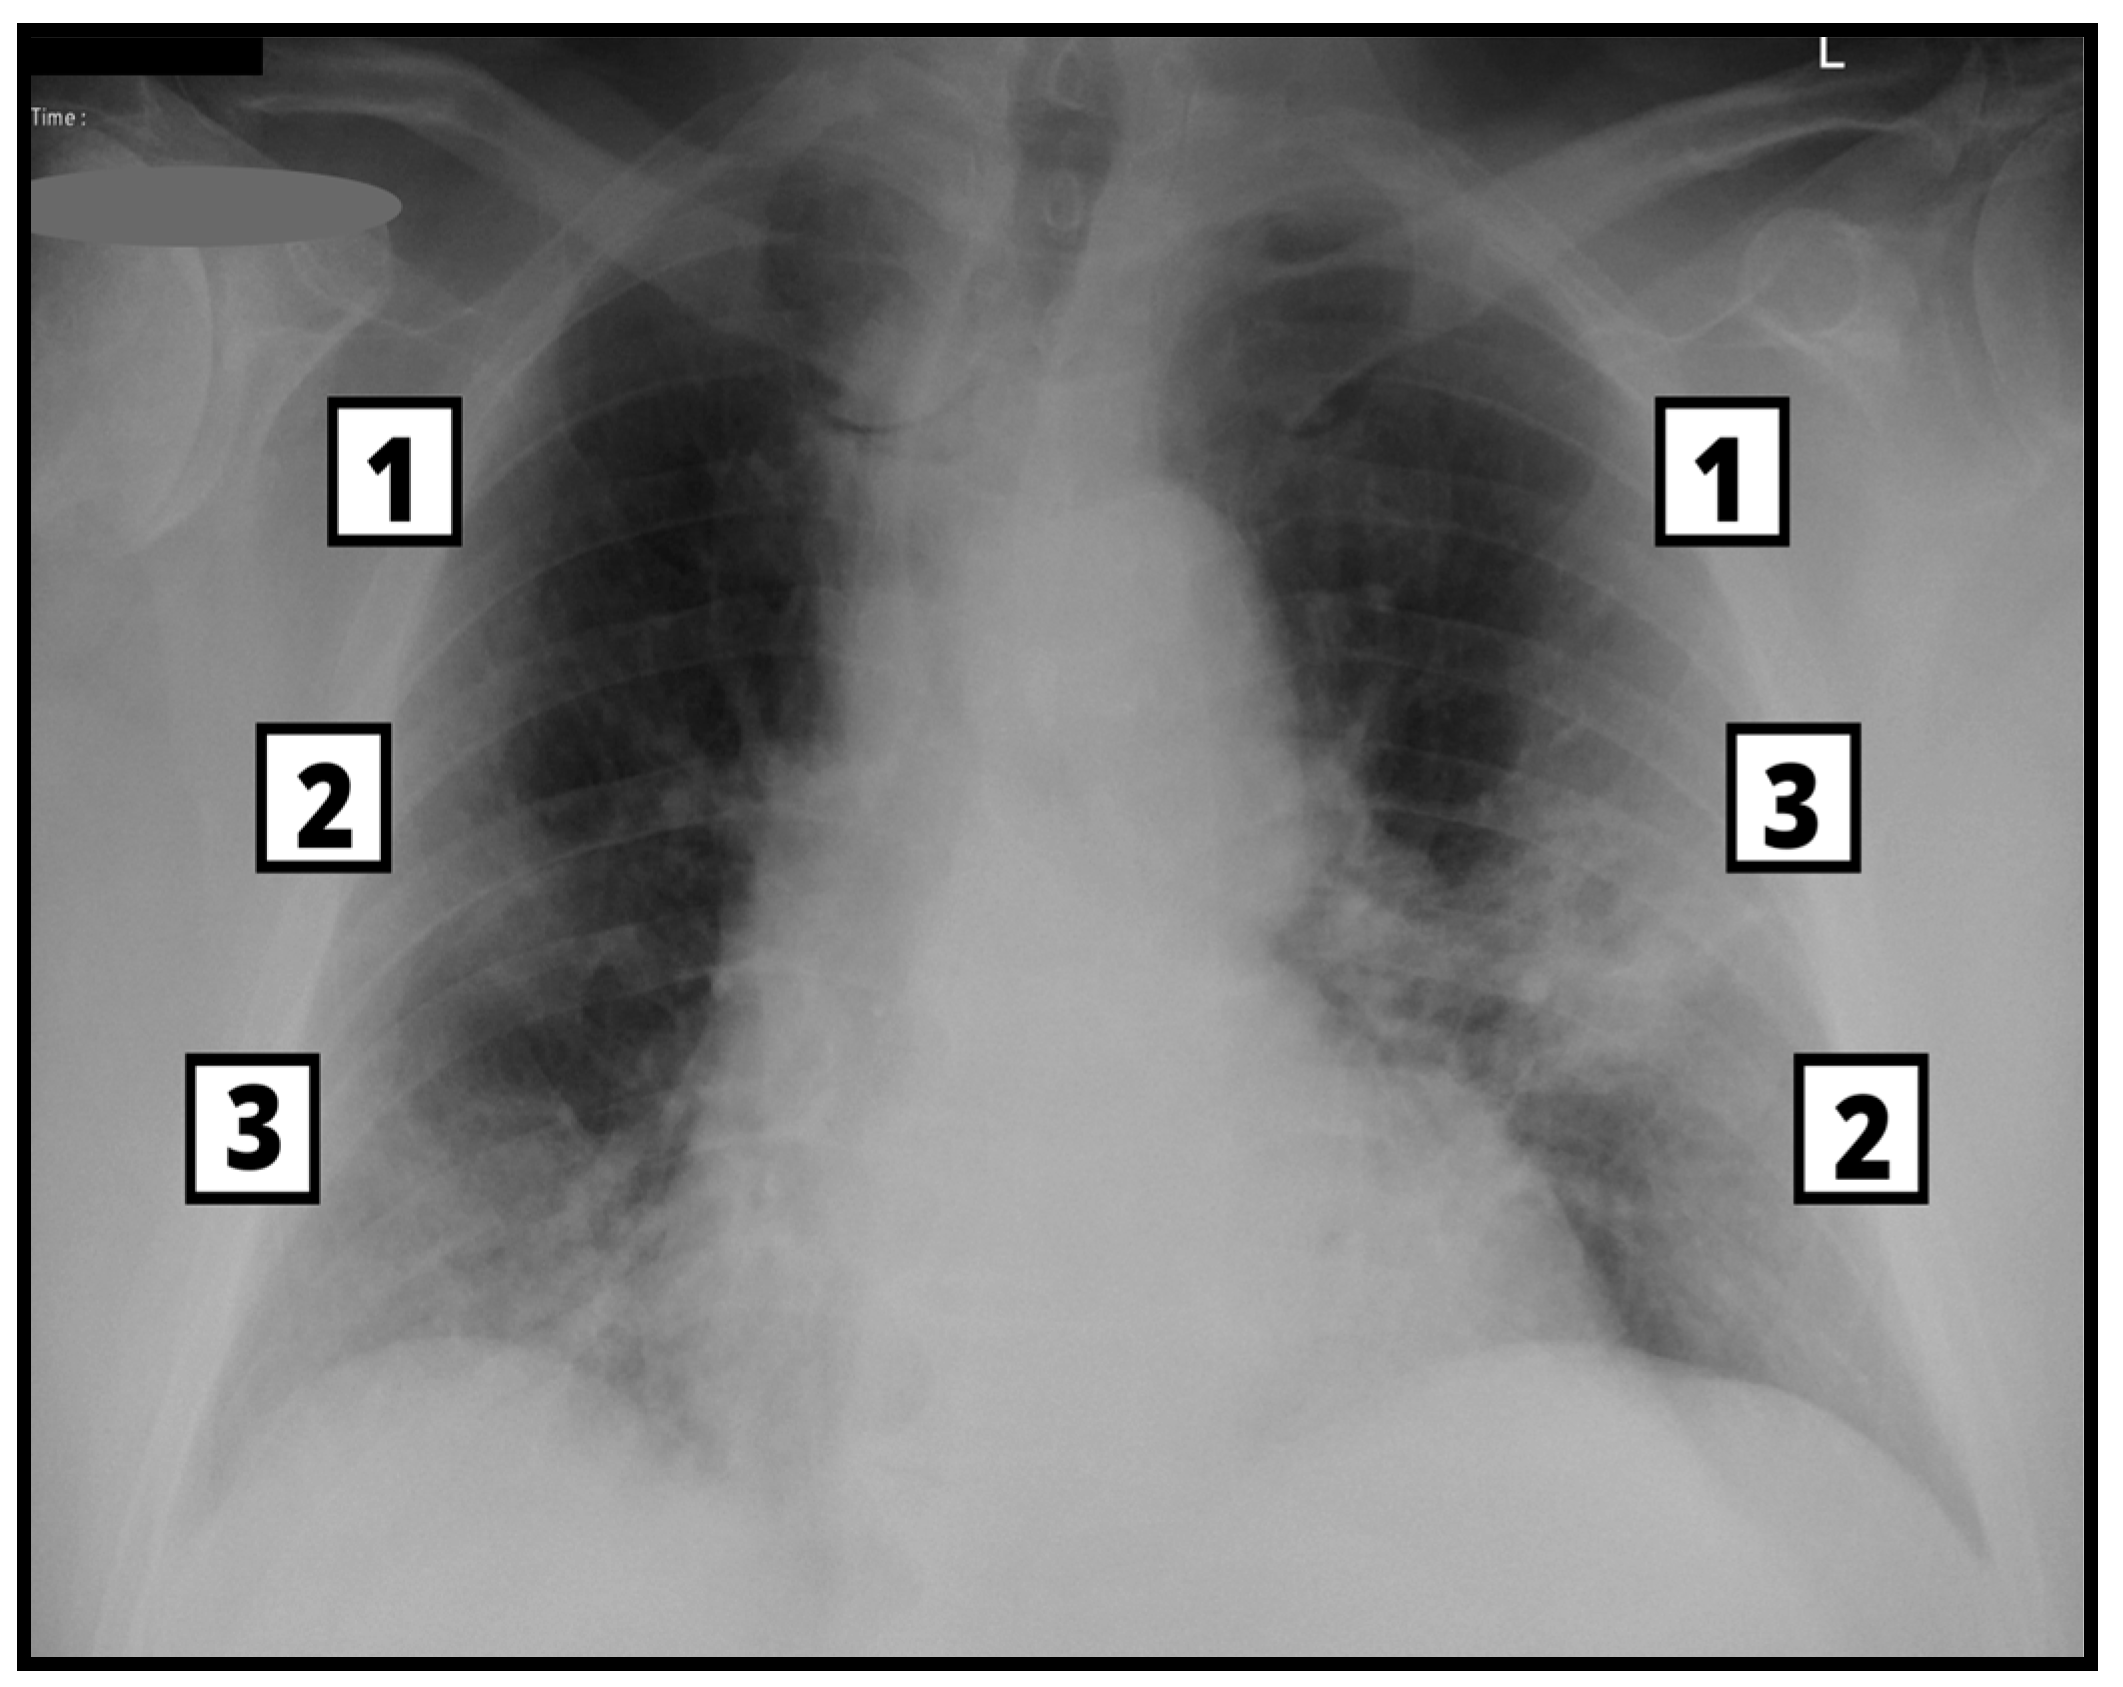

2.3. Imaging Acquisition and Analysis—CXR and CT

3.3. Brixia Score